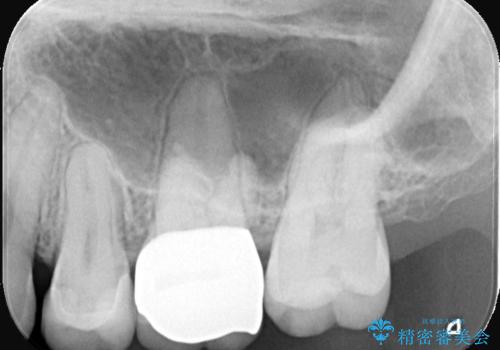

- 左上6番の奥歯のコンタクト下カリエス(歯と歯の間の虫歯)を主訴にご来院されました。レントゲンと精密診査の結果、歯と歯の間という、再発しやすい部位の虫歯であることが判明。患者様のご希望と口腔内の状態を考慮し、虫歯を徹底的に除去し、精密で再発リスクの低いセラミッククラウンで修復する治療計画を立案しました。これにより、見た目の美しさだけでなく、長期的な歯の健康維持を目指します。